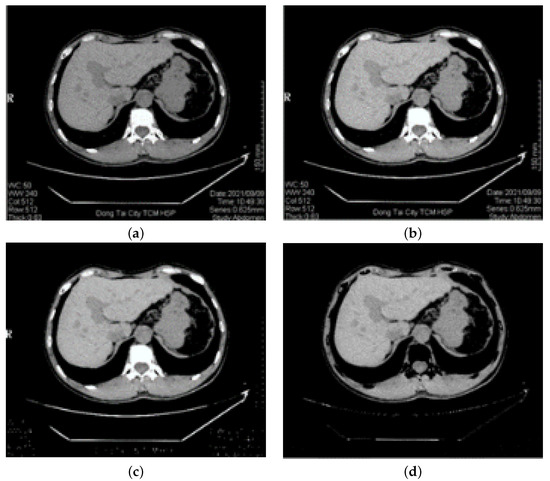

Consequently, this paper proposes a new process to optimize the performance best: (1) First, we distinguish the gray value of the image after clustering and set the threshold value through the gray value range of the image for binary segmentation. (2) Then, we use the reconstruction method based on four neighborhoods to grow the binarized image. (3) Finally, we fill the hole in the reconstruction result. Experimental results are shown in Figure 4: (a) the seed point selection; (b) the regional growth result of the original image without SFCM clustering; (c) the regional growth result of the image with SFCM clustering; (d) the regional growth result of the method in this paper. Note that the results of (b–d) are obtained from the same seed points. It is obvious that the result is better with SFCM clustering than the one without, and the operation taken in this paper can obtain the result closer to the liver boundary.

Figure 4.

Comparison results of regional growth of the same seed point: (a) the seed point selection; (b) the regional growth result of the original image without SFCM clustering; (c) the regional growth result of the image with SFCM clustering; (d) the regional growth result of our method.